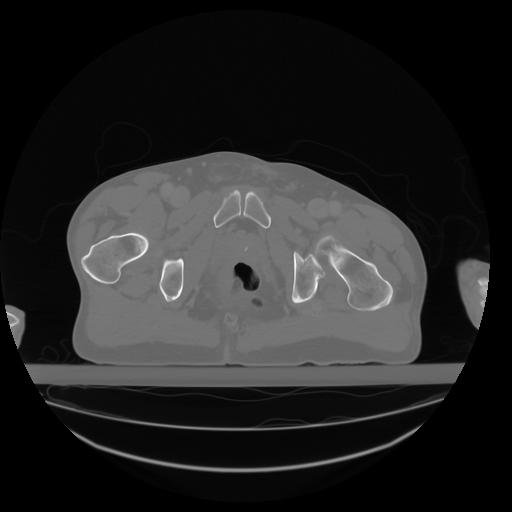

27 CUERPO,CE,Axial,3.0,CUERPO,,